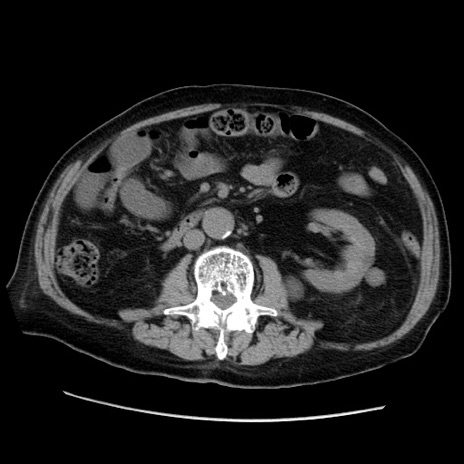

症例21(横断像)

【症例】70歳代男性

【主訴】腹痛

【現病歴】肝硬変・肝細胞癌にてかかりつけの方。約9時間前に食後より腹痛出現。症状が徐々に増悪し、嘔吐出現したため来院。

【既往歴】肝硬変、肝細胞癌(RFA、TACE後)

【身体所見】意識清明、表情苦悶様、BT 36℃、BP 129/78mmHg、P 88bpm、SpO2 97%(RA)、右上腹部から心窩部にかけて圧痛あり、反跳痛なし、筋性防御あり。

【データ】WBC 5800、CRP 0.16